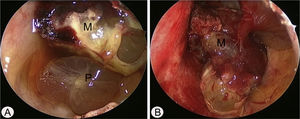

Case reportA 17-year-old male was referred to our outpatient clinic because of recurrent epistaxis after left nasal polypectomy. He had undergone nasal polypectomy due to nasal congestion at a local clinic 10 days ago. He had neither other symptoms nor any medical history. There was no history of trauma and no sign of allergy. The endoscopic examination revealed bulging of lateral nasal wall and bleeding due to left maxillary sinus mass (Fig. 1A). A Computed Tomography (CT) scan of the paranasal sinuses showed heterogenous enhancing mass in left maxillary sinus without adjacent bony involvement (Fig. 1B and C). On Magnetic Resonance Imaging (MRI), the mass expanding left maxillary sinus had mixed high signal intensity on T1-weighted images (T1WIs) and heterogenous high signal intensity on T2-weighted images (T2WIs) with an avid enhancement (Fig. 1D–F). Considering the location of tumor, surgical access was gained via Caldwell-Luc approach under general anesthesia because transnasal endoscopic sinus surgery had high risk of bleeding. The mass was originated from medial wall and partial superior wall of left maxillary sinus (Fig. 2A and B). The base of the lesion including the healthy mucosa around it was successfully removed with harmonic scalpel and microdebrider under direct visualization using a nasal endoscope and cauterized using suction cautery for prevention of recurrence (Fig. 3A). Histopathologic examination showed variable sized and irregular shaped vascular spaces with thrombus, consistent with arteriovenous malformation (Fig. 3B). Postoperative course was uneventful and he was discharged five days after surgery. Endoscopic examinations and CT performed 3 months postoperatively showed no evidence of recurrence.

Intraoperative endoscopic findings via Caldwell-Luc approach. (A) The polypoid mucosa (P) was detected in the inferior portion of left maxillary sinus. (B) After removal of polypoid mucosa, highly vascular mass (M) was originated from the medial and partial superior wall of left maxillary sinus.